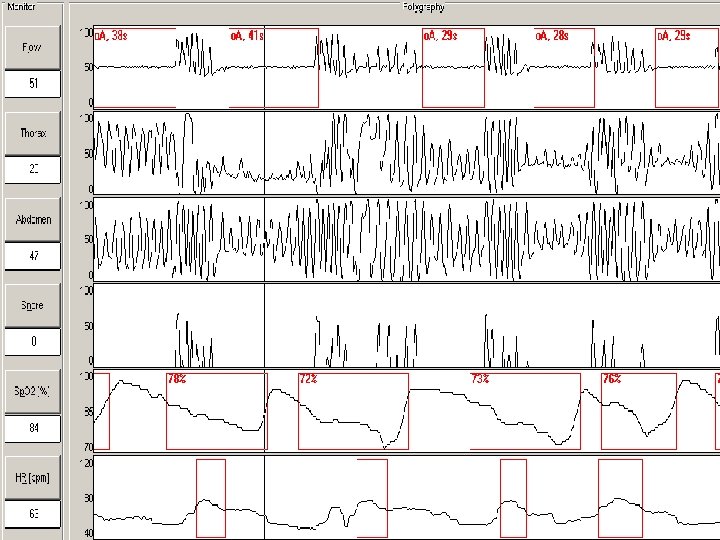

POLYGRAPHY • Airflow • Tracheal mycrophone • ECG • Thoracic belt • Abdominal belt • Pulse-oxymeter • Tibial EMG Spitalul Clinic de Pneumologie Iasi – D. Boisteanu

DIAGNOSIS OF SLEEP APNEA • To diagnose OSAS, the breathing pattern during sleep is analyzed for the presence of episodes of breathing cessation (apneas). • The total number of apneas divided by the total sleep time represents apnea index (AHI). • The cut off level for OSAS diagnosis is: AHI > 5/hour

Apnea-Hypopnea severity • AHI<5 Normal • AHI 5 -15 Mild OSA • AHI 15 -30 Moderate OSA • AHI >30 Severe OSA

DIAGNOSIS OF SLEEP APNEA • • • The gold standard for diagnosis of OSAS is nocturnal polysomnography, a simultaneous recording of several physiologic parameters: brain waves, eye movements, muscle activity, chest movements, air flow, and blood oxygen saturation - that must be performed by trained technologists using expensive equipment